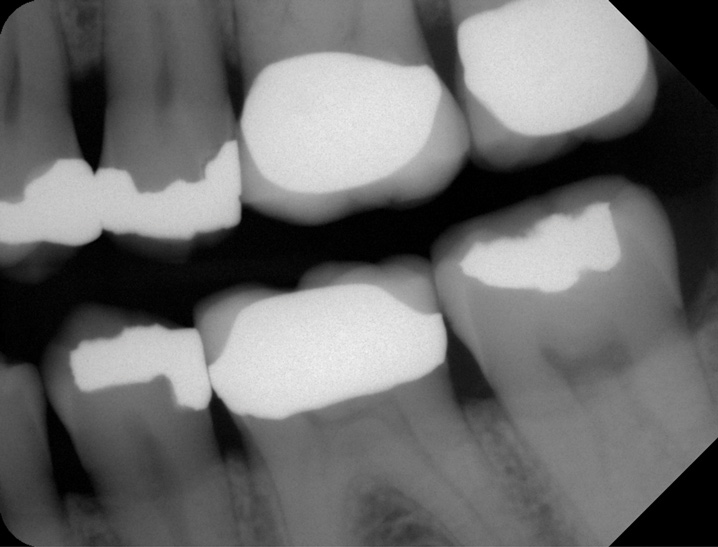

Another consideration is mean vertical displacement of unhampered posterior teeth, which in some studies was minimal: 0.8 mm37 and 0.9 mm30 (Table 1). Yet, there could have been sites where the amount of extrusion was clinically relevant. When Lindskog-Stokland et al assessed the risk of over-eruption using 1 mm as a threshold, they stated there was an odds ratio of 3.3 that unimpeded molars would extrude 1 mm compared to opposed molars.30 Based on their calculations, however, it is unclear which patients with a missing molar are at risk of over-eruption (Figure 1 through Figure 4). Indeed, if susceptible individuals could be identified, then restorative therapy could be initiated to stabilize their occlusion (eg, tooth replacement). Furthermore, odds ratios can be highly misleading, and predictive values would provide clinicians a better perspective as to what percentage of sites may experience significant extrusion.41,42

Fig 3. Patient No. 1, contralateral side; in 2009 patient presented with teeth Nos. 15 and 18. Subsequently, tooth No. 18 was extracted due to tooth fracture.

Figure 3

Fig 4. Patient No. 1 in 2016, with extrusion of tooth No. 15. Two different experiences in the same mouth, as shown in Figs 1–2 and Figs 3–4, underscore the unpredictability of extrusion.

Figure 4